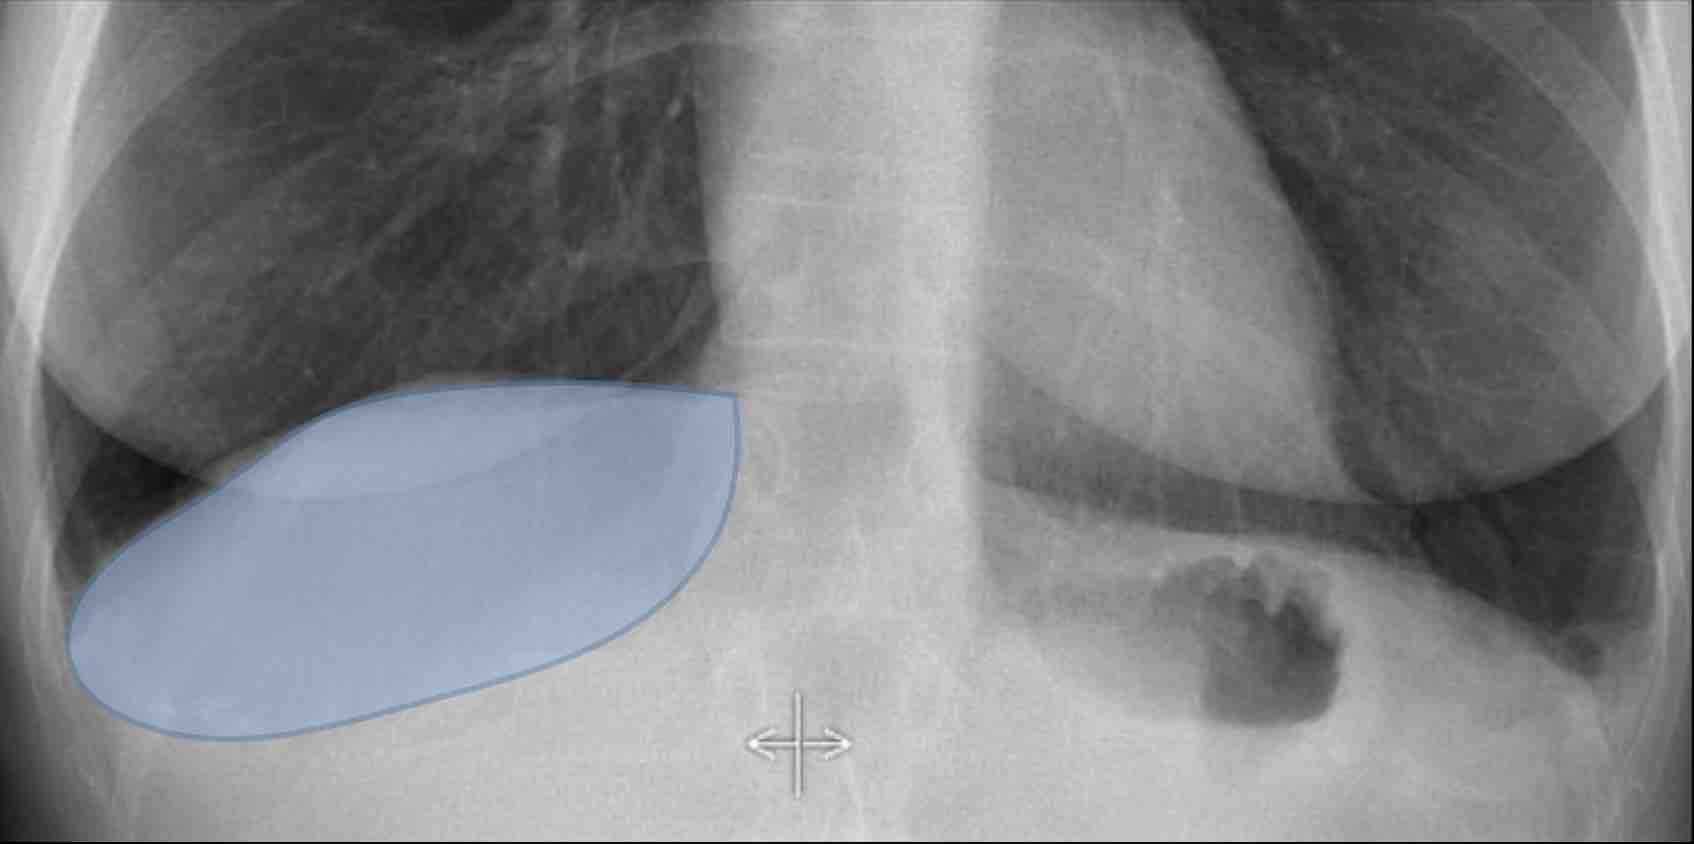

Vùng Khuất (2): Tổn thương Thùy Dưới Phải

Ví dụ này minh họa một khối lớn ở thùy dưới phải khó nhận biết trên phim PA nếu không chú ý kỹ đến các vùng khuất.

- Khi quan sát ban đầu, tổn thương không rõ ràng.

- Tuy nhiên, khi tập trung xem xét vùng dưới hoành và vùng sau tim, bất thường trở nên rõ ràng hơn.

- Phóng to hình ảnh để quan sát tốt hơn.